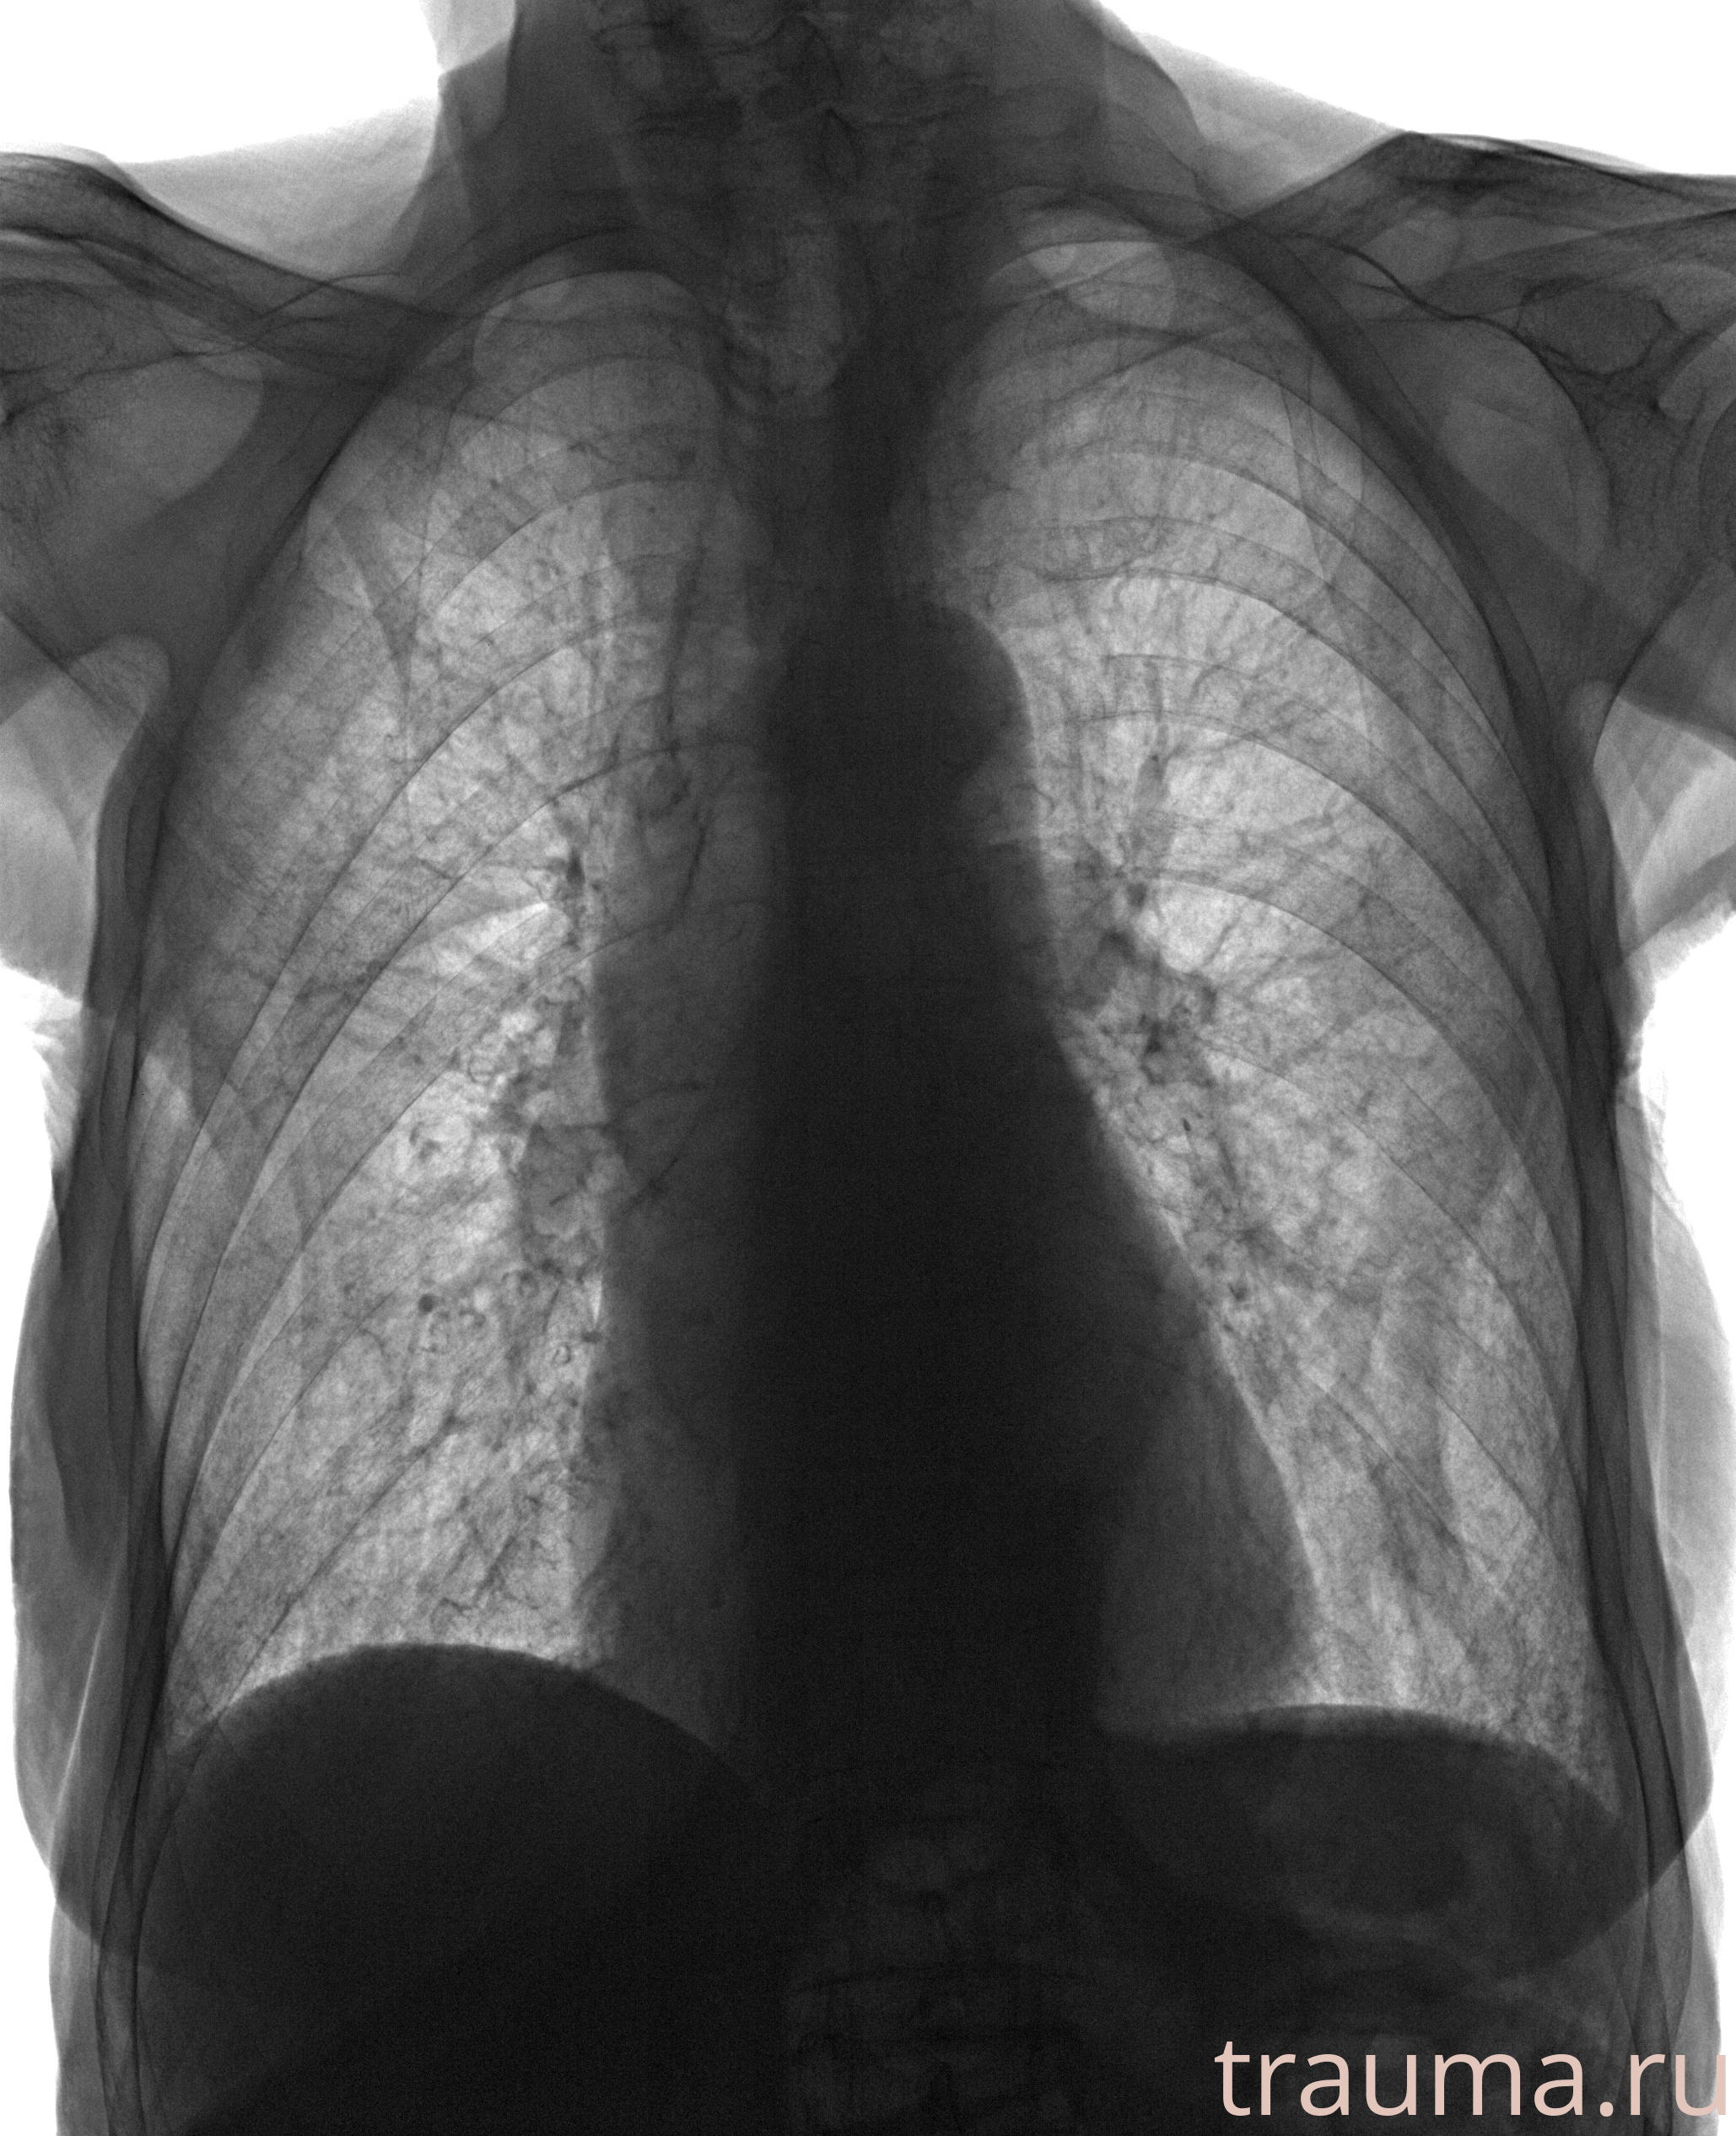

Рентген на дому: по вашему адресу приезжает врач-рентгенолог, травматолог-ортопед с мобильным рентгеновским аппаратом, проводит диагностику травмы или заболевания, делает необходимые рентгенограммы, дает рекомендации по дальнейшему лечению. Получить качественные снимки в домашних условиях возможно благодаря уникальной методике, разработанной МосРентген Центром для института  Склифосовского

при переломе шейки бедра и пневмонии от компании МосРентген Центр - партнера Института имени Склифосовского